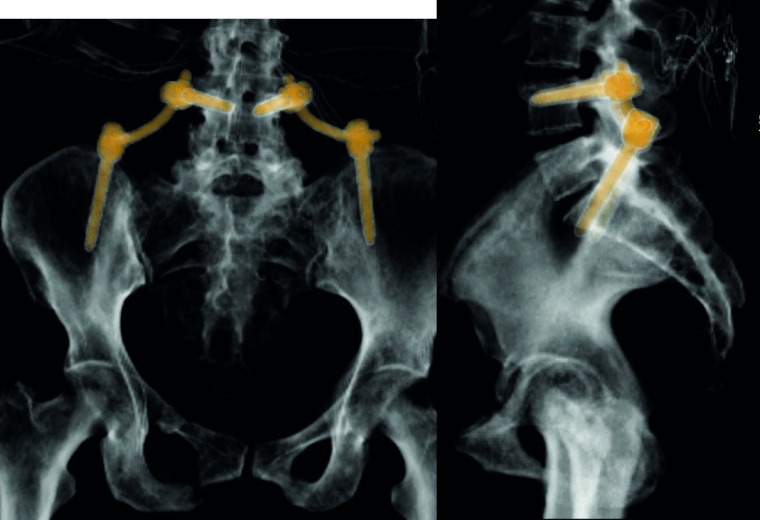

Sakrummetastasen: Stabilitätsgefährdende Metastasen am Sakrum (Abb. 3a) und am hinteren Beckenring werden zumeist mit einer mono- oder bilateralen vertebropelvinen Abstützung versorgt (Abb. 3b). Insbesondere das Os sacrum kann so aus der lasttragenden Kette herausgenommen werden. Vor allem bei Mammakarzinommetastasen kann mit der nachfolgenden Radiatio häufig eine so stabile Rekalzifikation erzielt werden (Abb. 3c), dass mitunter bei Beschwerden über dem Fixateur besonders bei schlanken Patienten eine Metallentfernung erwogen werden kann. Sollte das dorsale Os ileum mit betroffen sein (Abb. 4a) kann bei entsprechenden anatomischen Voraussetzung (Abb. 4b) auch weiter ventral auf den Beckenkamm abgestützt werden (Abb. 4c).